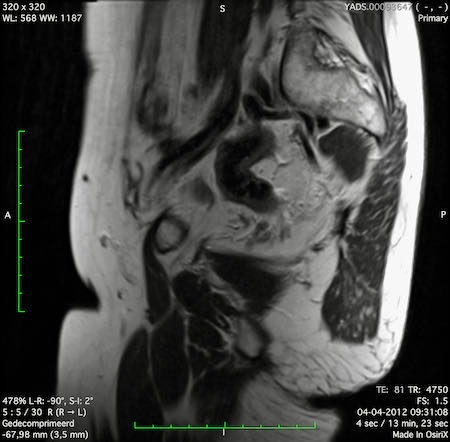

Hình ảnh

Các hình ảnh được cung cấp cho thấy ung thư biểu mô tế bào nhẫn với tình trạng dày lan tỏa thành trực tràng, hình ảnh bia bắn điển hình, và sự xâm lấn mỡ mạc treo trực tràng.